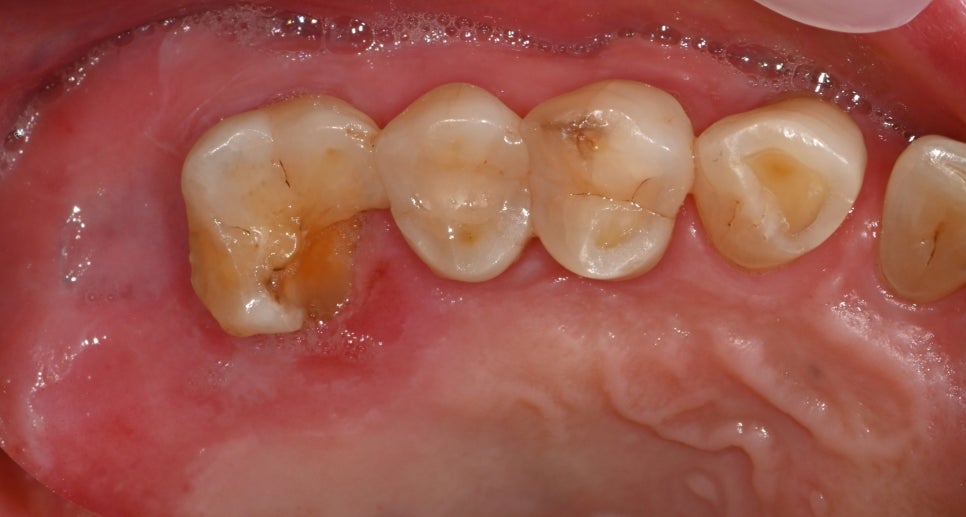

1.치근 파절 여부

뿌리 쪽까지 금이 퍼져 있어

남겨둘 수 없는 상황이었습니다.

2.주변 잇몸뼈의 흡수 정도

오랜 기간 반복된 염증으로

인해 뼈가 일부 줄어든 상태였습니다.